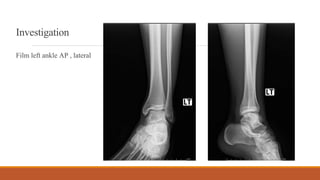

Investigation

Film left ankle AP , lateral

Film left ankle mortis